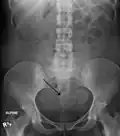

Two calcified fibroids (in the uterus)